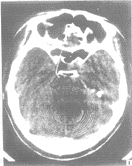

2.4 小脑蚓部髓母细胞瘤1例 患者年龄仅12岁,头痛、呕吐症状较明显。当地CT片质量较差,但隐约可见小脑蚓部有一个稍高密度的肿块影(图5)。本院MR显示肿块约3cm×4cm大小,T1W稍低信号,T2W呈稍高信号,明显增强(图6)。

图5 小脑蚓部髓母细胞瘤,小脑蚓部有一略高密度肿块影,但被忽视